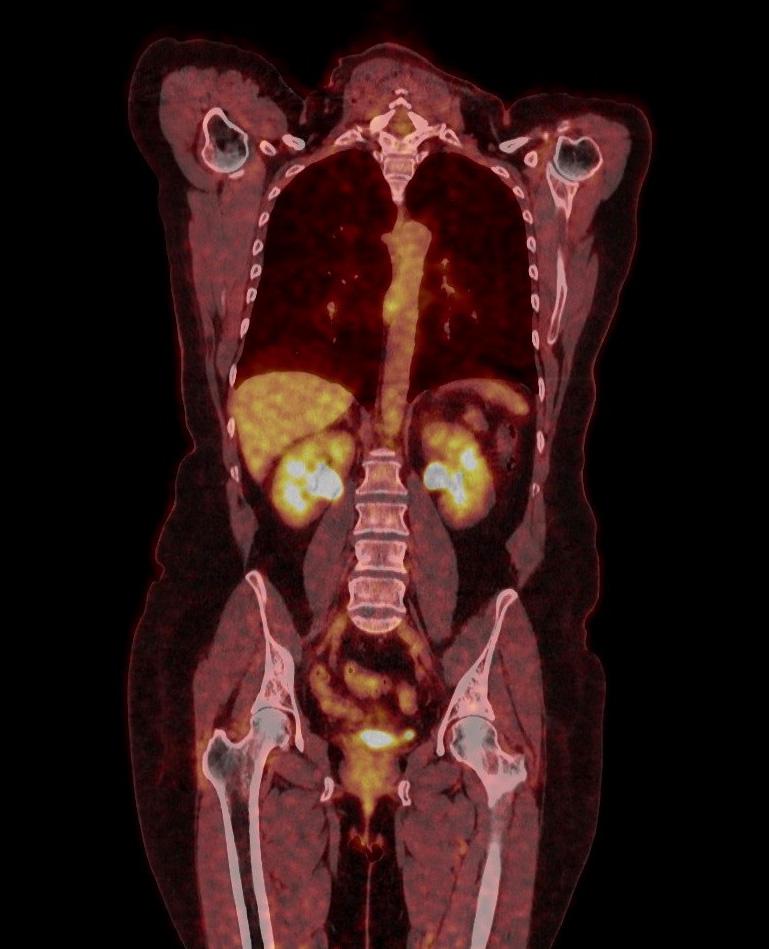

TEP-SCAN

Tomoscintigraphie par émissions de positons

La TEP-scan (Tomographie par Emission de Positons couplée à un scanner) est un examen d’imagerie médicale performant qui s’intéresse au fonctionnement, au métabolisme et à l’anatomie des organes.

Cet examen intervient dans différents domaines (cancérologie, rhumatologie, orthopédie, médecine interne) et peut permettre de détecter un cancer ou ses métastases, une inflammation ou une infection, d’évaluer la présence ou l’étendue d’une maladie, comme le cancer ou certains rhumatismes. Il pourra aussi permettre au médecin prescripteur de choisir un traitement adapté à votre maladie et / ou d’en évaluer l’efficacité et aussi de prouver une guérison.

Pour la réalisation des images, vous serez allongé sur le dos sur la table d'examen. L’appareil comporte un anneau, un peu plus large que celui d’un scanner, dans lequel la table d’examen va avancer afin de réaliser des images de votre corps, en général de la tête jusqu’à mi-cuisse, pendant environ 12 minutes.